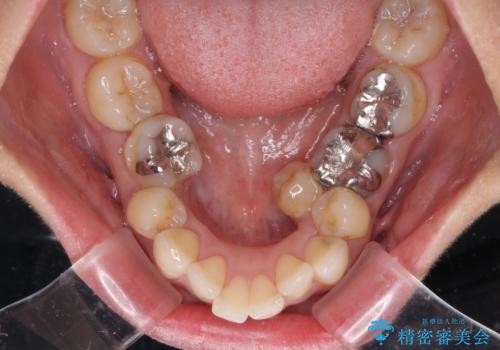

- 歯列全体が内側に倒れ込んでいることと、口元の突出感を気にして来院された患者様です。

上下ともに歯列が狭窄しており、前方に突出している状態でした。

歯が重なるような叢生も認められたため、上下左右の第一小臼歯4本を抜歯して、口元が引っ込むように治療を行うこととしました。